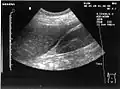

A normal ultrasonographic view of Morison's pouch. The bright line is the capsule of the kidney; there is no fluid present and hence no visible space. A normal ultrasonographic view of Morison's pouch. The bright line is the capsule of the kidney; there is no fluid present and hence no visible space.